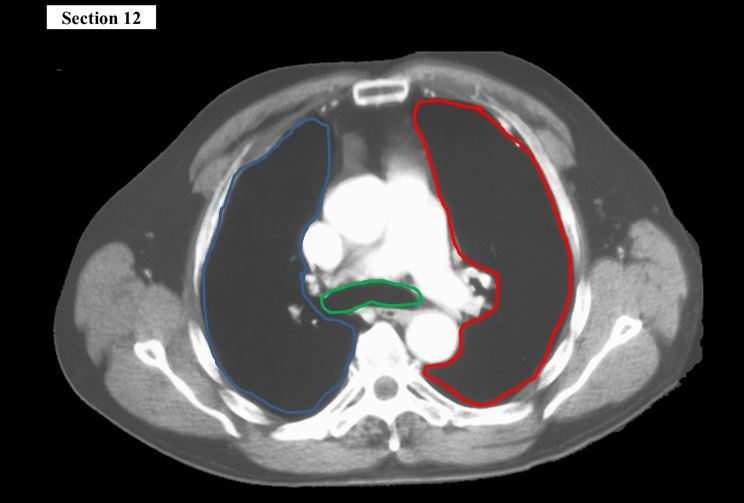

12

Q

The blue organ is the _____

The yellow organ is the _____

A

right lung

left lung

How well did you know this?